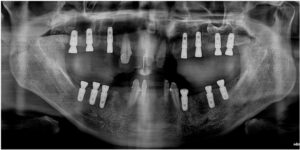

양산전체임플란트를 진행하기에 앞서

파노라마 사진과 3D CT 촬영을 통해

잔존 치조골의 양과 두께,

상악동과의 거리, 하치조 신경의 위치,

눈에 보이지 않는 해부학적 구조물 등을

면밀하게 파악하는 과정을 통해

임플란트를 식립하기 좋은 위치와

식립 될 Fixture의 길이와

두께를 선정하였으며,

식립 후 일주일 체크에서

아래턱 오른쪽 첫 번째 어금니(#44i)가

흡연으로 인한

골 유착 실패와 치조골 흡수로

잔존 치조골과 제대로 결합이 되지 않아

제거가 필요한 상황이었으며,

해당 부위 임플란트 Fixture 제거 후

충분한 시간이 지났을 때

체크 후 재 식립을

도와드리기로 하였으며

흡연으로 인한 골 유착 실패로 제거 한

아래턱 오른쪽 첫 번째 작은 어금니(#44i) 자리는

제거 후 2달이 지났음에도

치조골 상태가 좋지 않아

바로 옆의 두 번째 작은 어금니(#45) 자리에

임플란트 식립을 도와드리기로

치료 계획을 변경하였습니다.